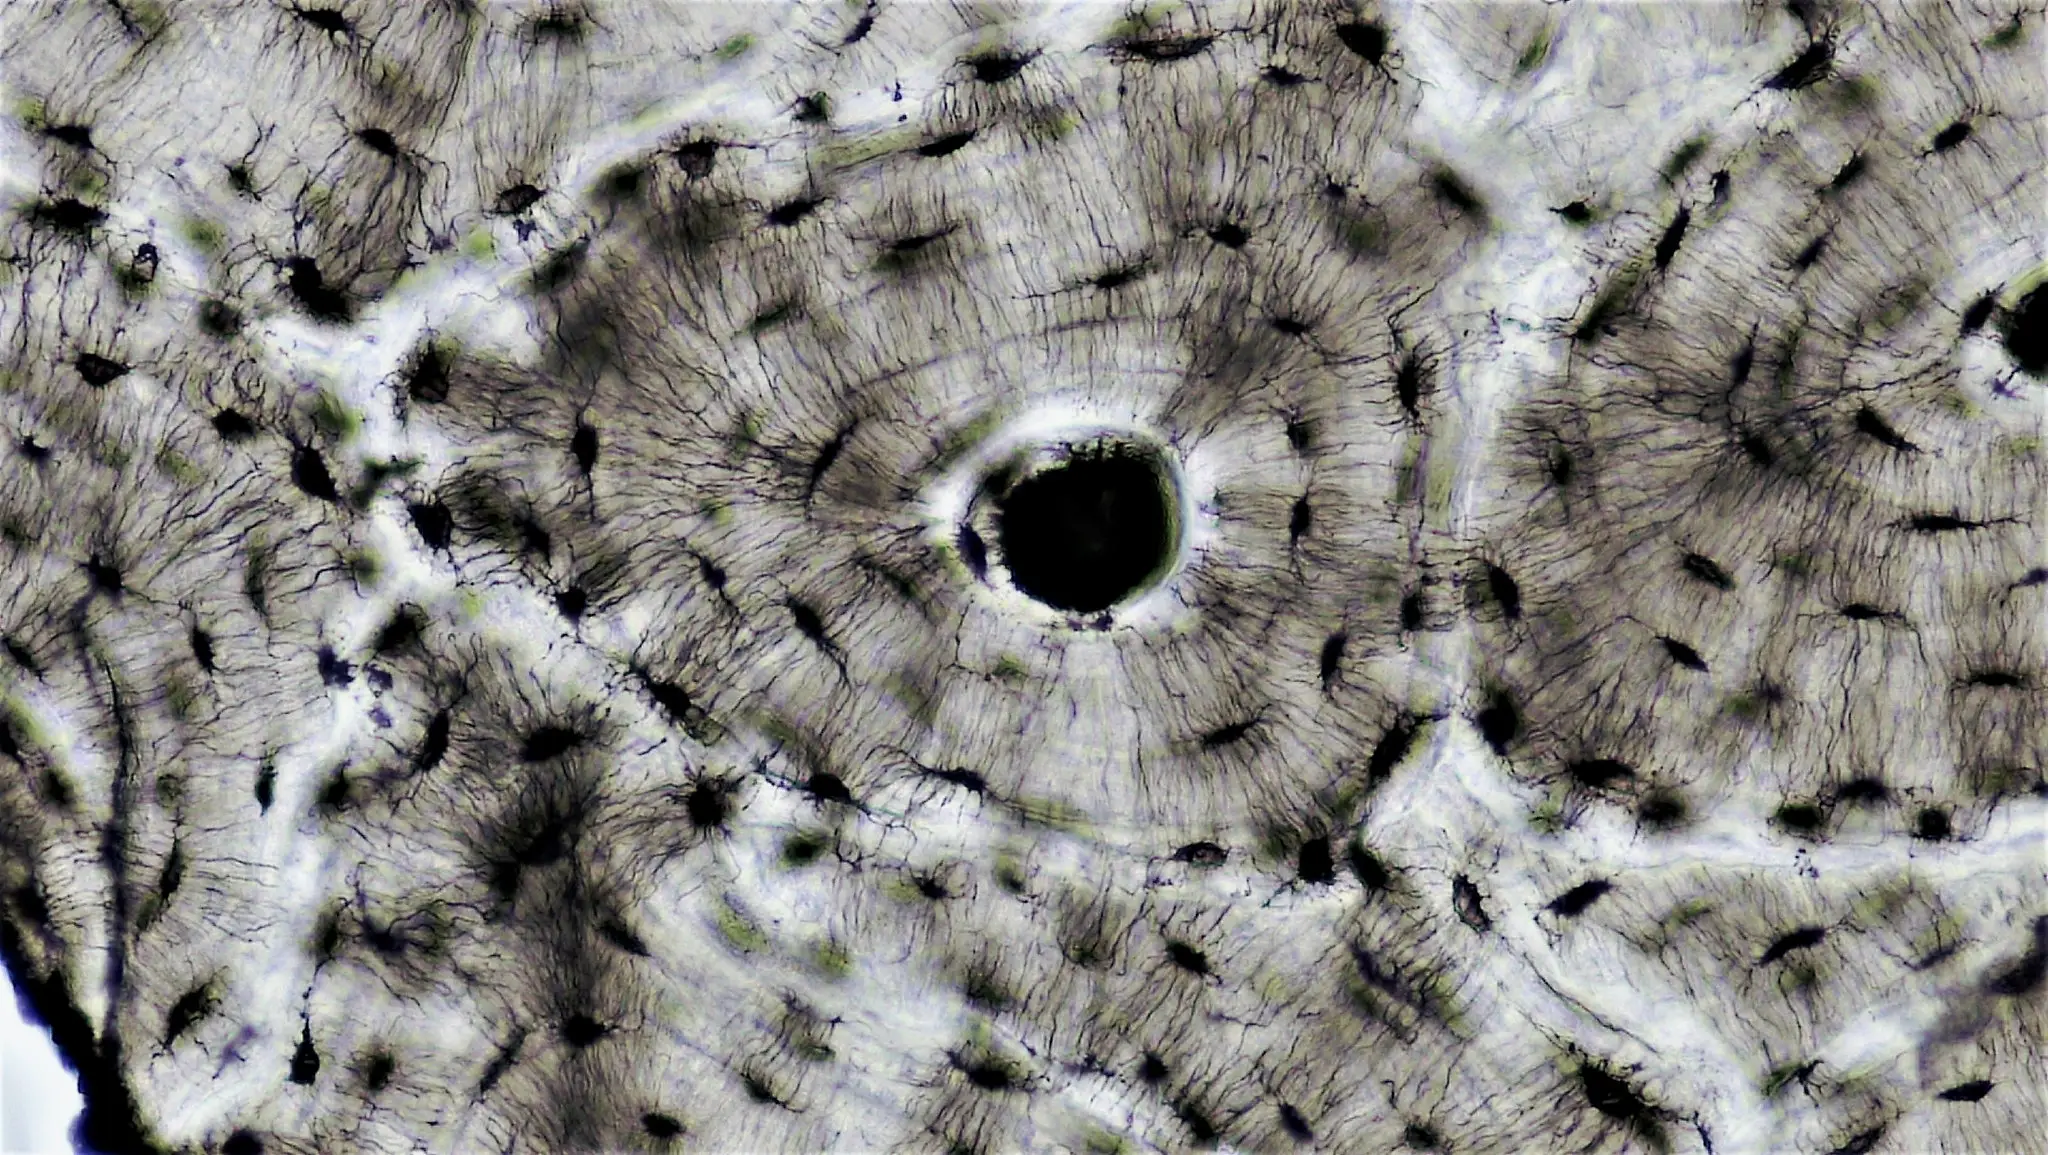

Diagramma illustrativo che mostra la trasformazione dei fibroblasti in miofibroblasti, evidenziando le caratteristiche cellulari e la produzione di matrice extracellulare.

Da 10.3390/cells10071794 licenza CC4.0